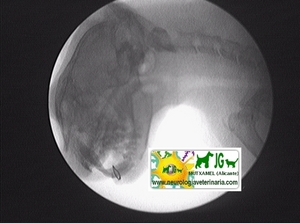

La radioscopia con intensificación y captura digital de imágenes ayuda en numerosas exploraciones neurodiagnósticas. Es la gran desconocida en medicina veterinaria, por su fama de cara (es más económica que un buen microscopio), es la “prohibida” del gremio (por desconocimiento de que no tiene nada que ver con las fluoroscopias que nos han hecho en el médico de pequeños), etc.. Gracias a ella capturamos foto-radiografías y vídeo-radiografías para su archivo en el historial médico del paciente. Debido a la baja potencia del aparato de rayos X necesaria, la irradiación es mínima, correspondiendo un minuto de exposición a la radiación emitida realizando 10 radiografías de forma convencional (y nunca se emplea un minuto en cada exploración). Como técnicas más utilizadas en nuestro hospital destacan: - realización de mielografías o discografías, en la cual estamos viendo la entrada de la aguja y la salida del contraste en el espacio subaracnoideo o en el disco. - mielografía dinámica: modificamos el plano scópico a nuestra conveniencia, observando, y grabando, la región anatómica que nos interese. - detección rápida de metales a animales a los que se les va a realizar una resonancia magnética. - estudio dinámico de las inestabilidades vertebrales. - diagnóstico de subluxaciones articulares (muchas veces imposibles de detectar con radiografía convencional): mandibulares, atlantoaxiales, miembros torácicos o pelvianos, etc.. - arteriografías cardíacas y periféricas. - portografías mesentéricas. - uretro-prostato-cistografías retrógadas. Y un largo etcétera. Como añadido tiene la posibilidad de obtención de archivos fotográficos JPG o videos AVI, los cuales se pueden luego transformar en otros formatos, y que se estudian con un editor de fotografías y vídeos, se envían por email, y numerosos procesamientos informáticos a nuestra conveniencia. Desarrollaré en breve : RADIOSCOPIA DEL CRÁNEO RADIOSCOPIA DE LA COLUMNA |